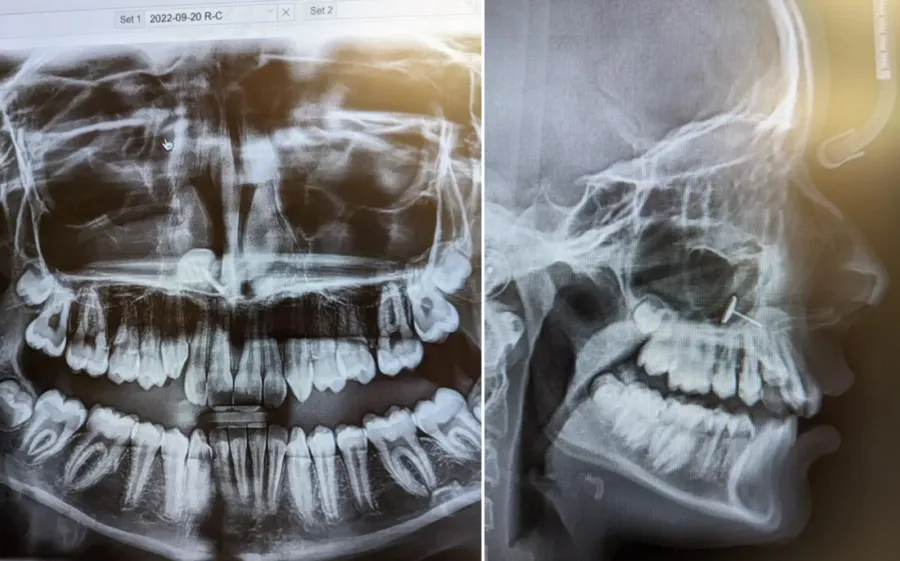

Kad je Amerikanka odvela svoju 13-godišnju kćer ortodontu kako bi započeli postupak ugradnje aparatića za zube, nije mogla ni zamisliti što će otkriti rendgenska snimka njezinih usta. Rutinski posjet zubaru neočekivano se zakomplicirao za majku i kćer iz Washingtona.

"Ortodont je ušao u sobu i na ekranu pokazao rendgenske slike," ispričala je majka za Newsweek. "Svi smo ih pogledali u isti trenutak i nekoliko minuta pokušavali shvatiti što uopće gledamo," dodala je.

Na snimci se vidio mali metalni predmet zaglavljen u kćerinim sinusima. Majka nije imala pojma kako je mogao završiti tamo, no jedna osoba u prostoriji točno je znala – njezina kćer.

"Uzela je naušnicu kojom su joj probušili uši i pokušala je progurati kroz nos," objasnila je. "Očito je u nekom trenutku pokušala gurnuti naušnicu iznutra prema van. Ne znam je li kihnula, ali na kraju ju je udahnula i ona se zaglavila u sinusima."

"Kad smo shvatili o čemu se radi i kako je tamo dospjelo, nazvala sam specijalista za uho, nos i grlo koji joj je prije nekoliko godina uklonio krajnike. Uz pomoć vrlo dugih medicinskih pinceta i mirne ruke uklonio je predmet. Kći tijekom zahvata nije osjećala bol i, s obzirom na okolnosti, sve je prošlo prilično dobro," zaključila je umirena majka.